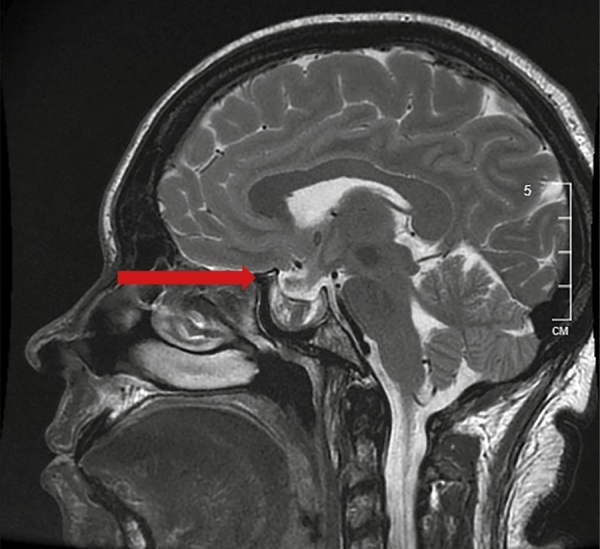

This article presents a literature review on the topic of remission of severe neuroendocrine diseases due to adenoma apoplexy. The discussion addresses possible mechanisms underlying apoplexy in pituitary adenomas. Additionally, two clinical cases of spontaneous remission of acromegaly and Cushing's disease in patients hospitalized at Endocrinology research Centre for neurosurgical treatment are discussed. These cases highlight the need for thorough examination and retesting of patients with hormonally active tumors immediately prior to neurosurgical interventions.